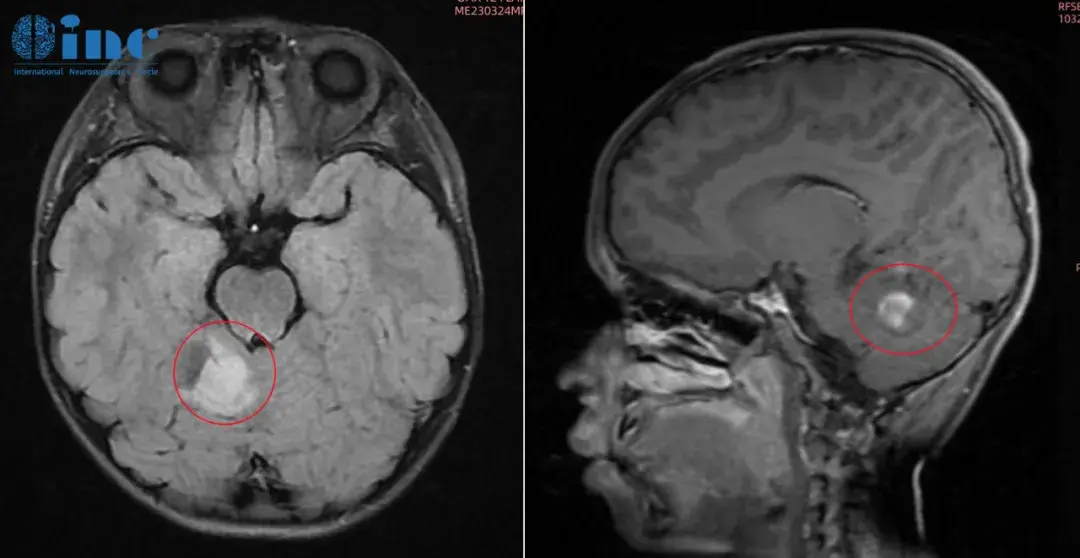

怀孕查出胶质瘤怎么办?可以做CT或者MRI吗?、生下来的孩子会健康吗33岁的凯莉在怀孕期间因严重头痛,走路不稳,记忆力减退等症状就医,MRI图像显示在她的两个侧脑室后部有一个巨大的囊...